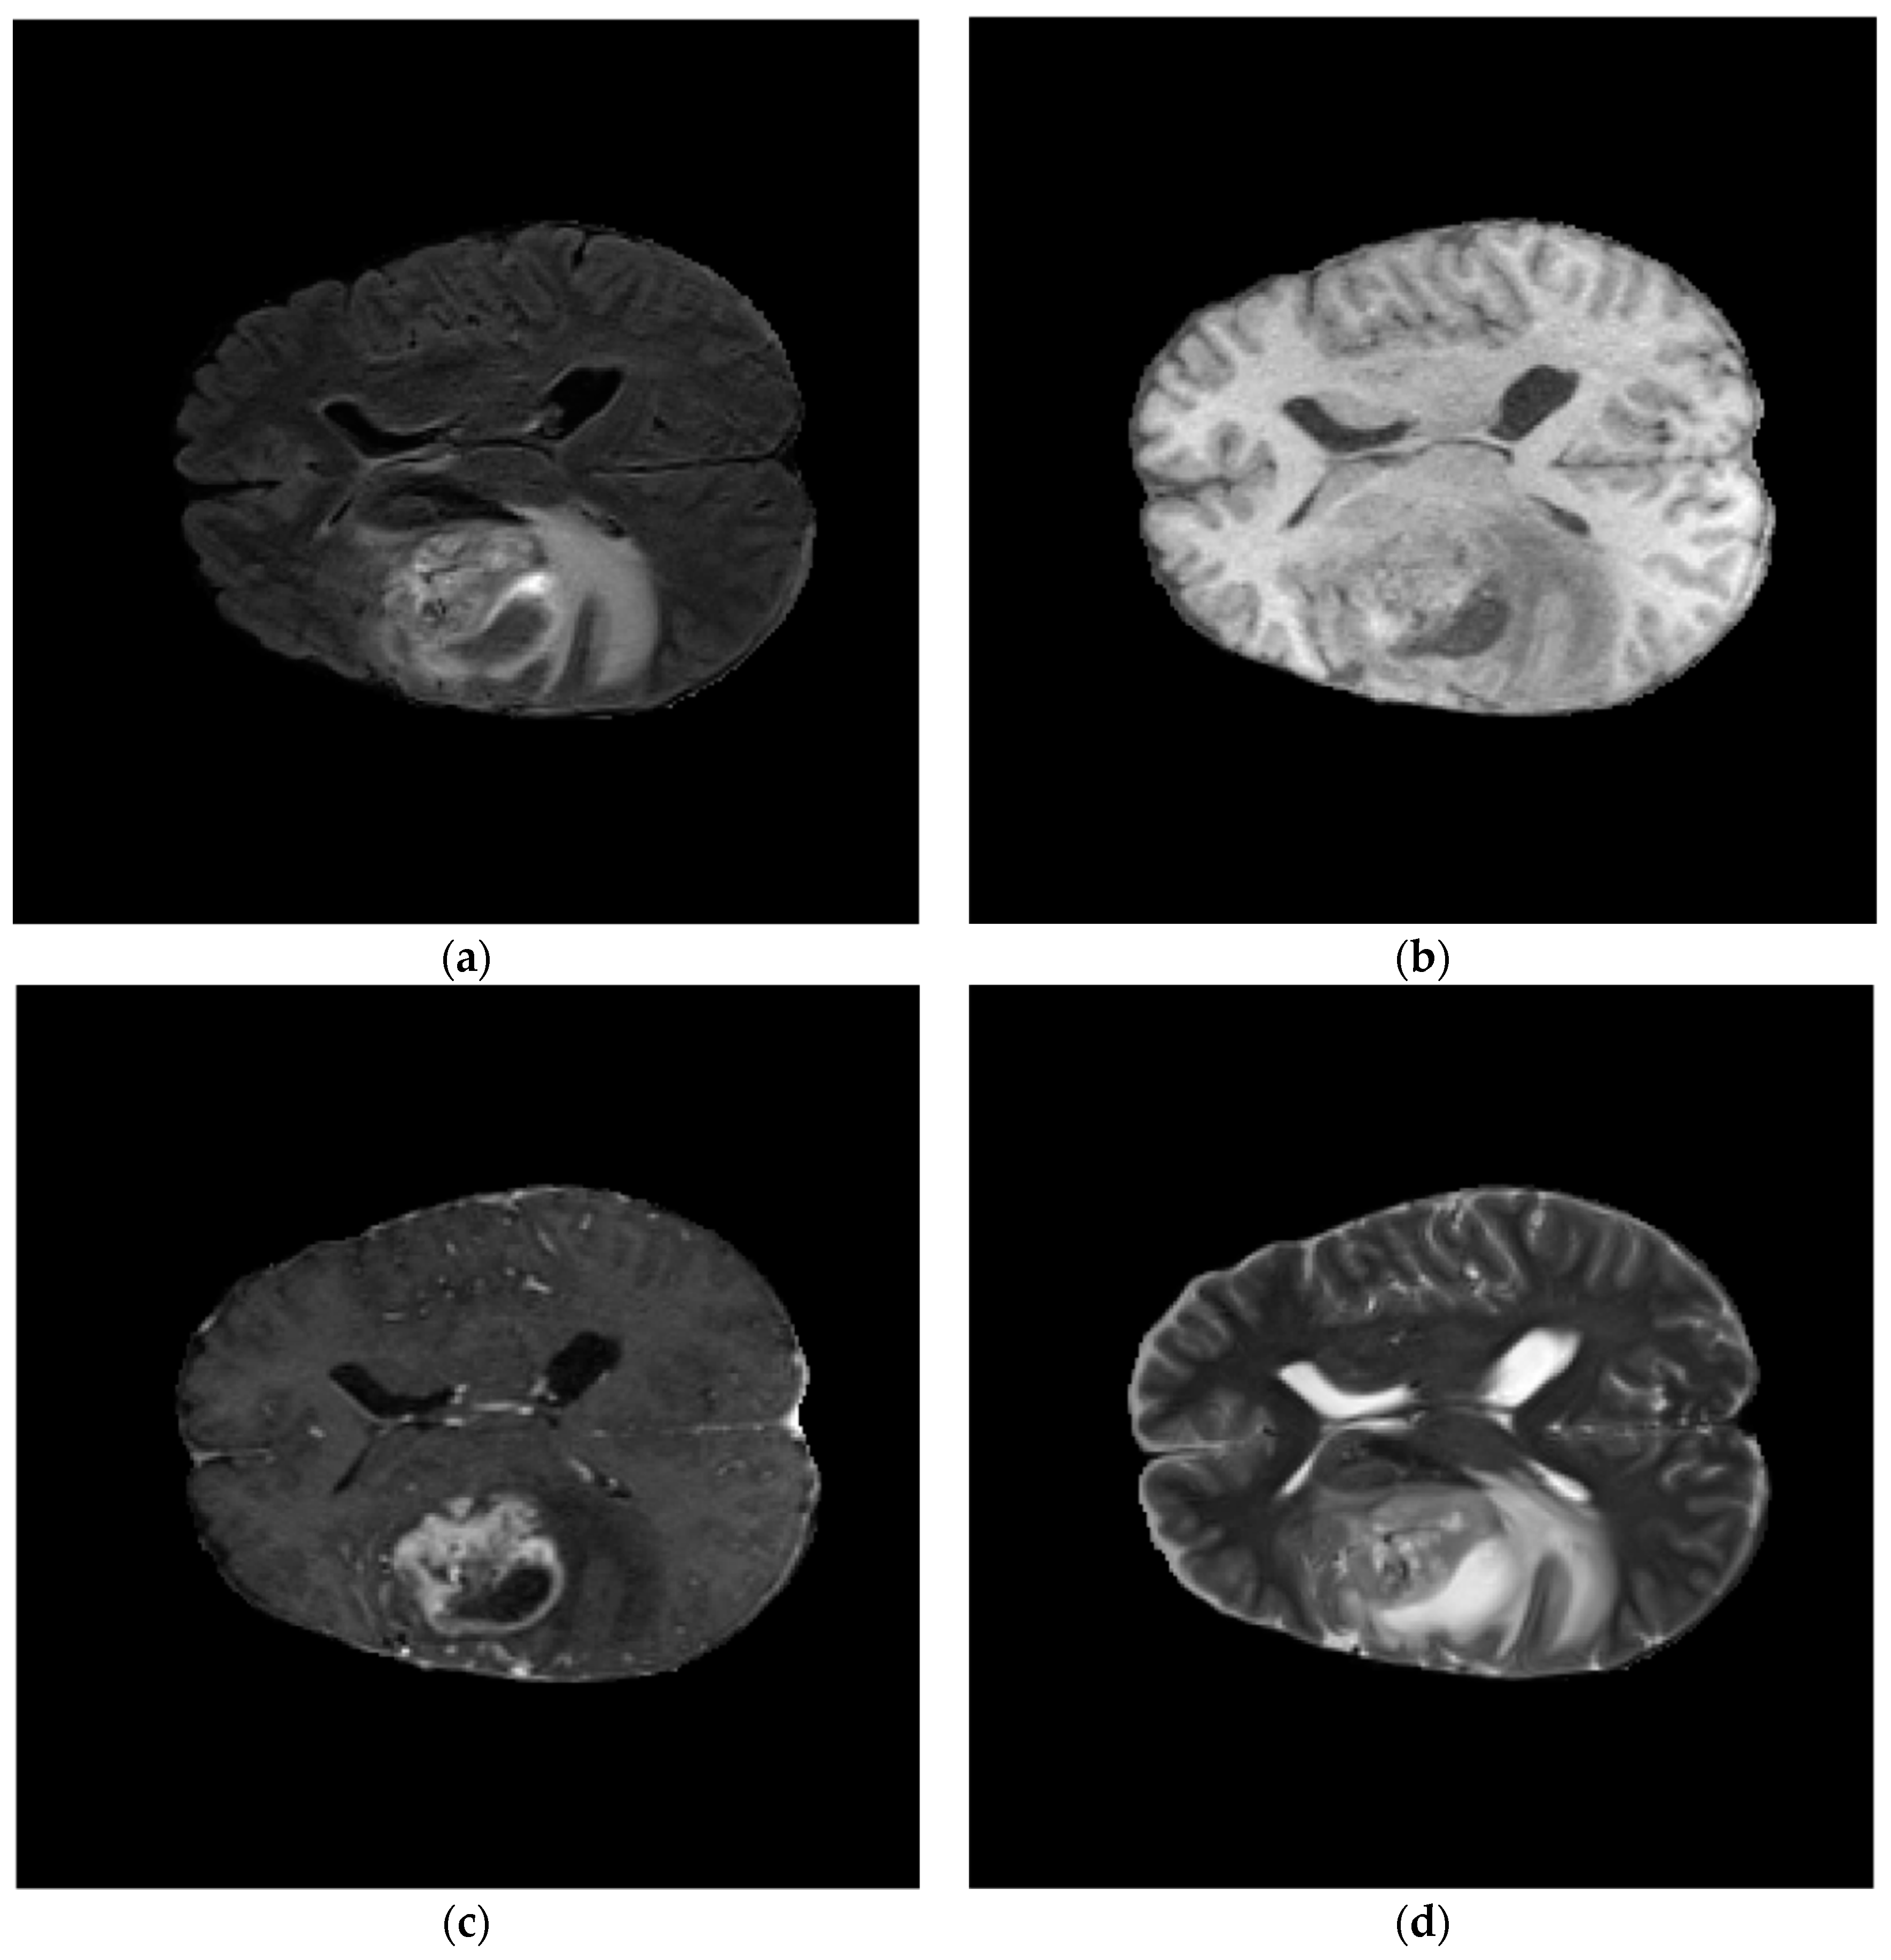

The public dataset of brain tumor segmentation challenge (BraTS Challenge) 2021 [25] is utilized to evaluate the segmentation accuracy of the proposed approach. It has a total of 2040 cases; 1251 of them are included in the training set cases, 219 of them are included in the validation set, and the remaining 570 cases are in the test set. Each case contains four modalities of MRI, as shown in Figure 6, where, T1 (T1-weighted images) modality can be used to show the anatomical structure of the tumor; T2 (T2-weighted images) modality can be used to detect edema, inflammation, etc.; the T1CE (Contrast-Enhanced Imaging) modality can show the internal condition of tumors and hemangiomas, and FLAIR (Fluid Attenuated Inversion Recovery) modality can better show the condition around the tumor as well as the edema area. The dimensionality of each modality is 240 × 240 × 155. Since the BraTS 2021 training set has labels, while the validation set and test set have no labels, the dataset is divided into a training set, a validation set, and a test set in a ratio of 8:1:1 to evaluate the segmentation accuracy of the proposed approach.

Figure 6. Examples of the four modalities of a case: (ad) are the FLAIR, T1, T1CE, and T2 modalities for the case.